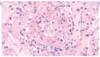

The provided image is an example of what pathology?

Acute Supperative Pericarditis

- Fibrinous & presence of pus

- Possible causes

- adjacent pneumonia

- can be infectious

- Photo on left

- extensive shaggy, purulent pericardial exudate arising from direct extensive from adjacent pneumonia

- Photo on right

- extensive deposition of fibrin (black curved arrows) on the pericardial surface, focal hemorrhage, and many neutrophils (black open arrow, top)